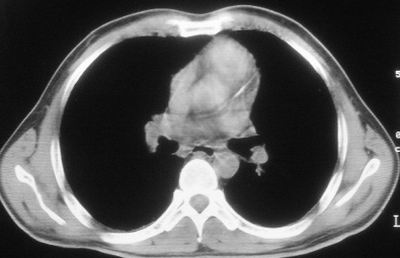

患者,男,44岁,糖尿病4年余,近期消瘦、乏力。化验检查:总胆红素26.33(参考值:5.1-17.2u mol/l),直接胆红素:6.4(参考值:0-4.3u mol/l),谷-丙转氨酶(alt):843(参考值:<40u/l),hbsag(+),抗hbs(-),hbeag(-),抗-hbe(+),抗-hbc(+)。

1\\粟粒性肺结核可能性大,支气管肺泡癌不排除

双肺散在小结节影,考虑粟粒性肺结核.肺窗薄扫会更好看些.

双肺外侧带胸膜下可见网状阴影,考虑轻度肺间质纤维化。

诊断:癌性淋巴管炎.

双肺纹理增强并可见网格状影达外带,考虑双肺感染并轻度间质纤维化

1.双肺急性粟粒型肺结核;2.少量腹水.

肺间质纤维化并肺部感染,结合不能排出,毕竟糖尿病人易合并之,建议结合ppd检查或hrct进一步扫描。